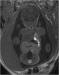

Abbildung 4: Pränatale Magnetresonanztomographie Fetus in der 32. SSW mit linksseitiger kongenitaler Zwerchfellhernie, koronale Schichtführung. Mit Hilfe der hier verwendeten Kontrastparameter können intrathorakal mit Mekonium gefüllten Darmanteile sehr hell dargestellt werden. Die Leber, sie ist etwas weniger hell als Mekonium, liegt intrabdominal. Am Hals ist auch die Glandula thyroidea zu erkennen. |

Abbildung 4: Pränatale Magnetresonanztomographie

Fetus in der 32. SSW mit linksseitiger kongenitaler Zwerchfellhernie, koronale Schichtführung. Mit Hilfe der hier verwendeten Kontrastparameter können intrathorakal mit Mekonium gefüllten Darmanteile sehr hell dargestellt werden. Die Leber, sie ist etwas weniger hell als Mekonium, liegt intrabdominal. Am Hals ist auch die Glandula thyroidea zu erkennen. |